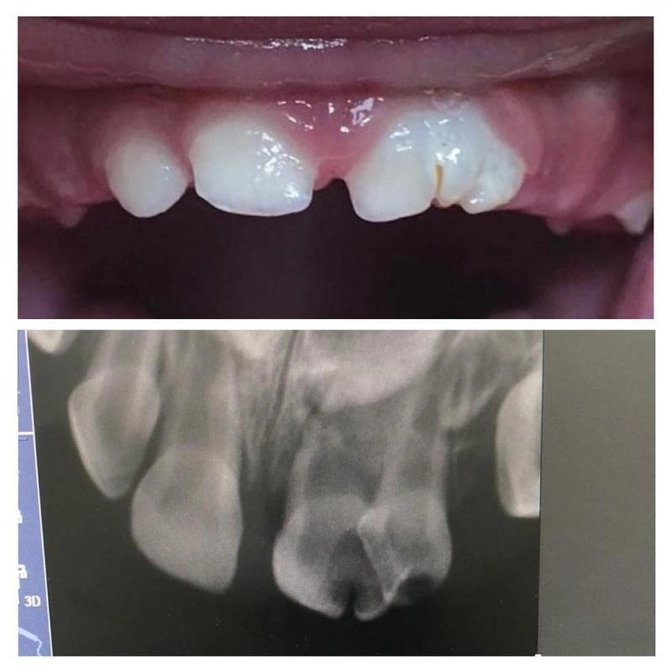

На картинке вы видите два зуба сросшихся в один.

Зубы молочные.

Малышу чуть больше года.

Это редкое явление, и почему так происходит до сих пор не ясно.

Возможно, в какой-то момент два зачатка просто слились в один.

Но здесь двойной зуб поразил кариес и он уже начал разрушаться.

Важно как можно раньше начать лечение.

Оно будет долгим, работа кропотливая, так как зуб особенный, сдвоенный.

Принято решение проводить сложное лечение в условиях медикаментозного сна.